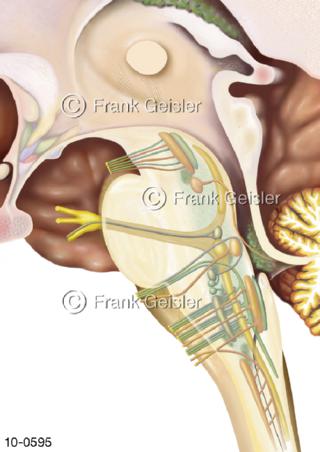

Bildergalerie Nervensystem

Bilder zum Nervensystem,dem Gehirn, Teil des zentralen Nervensystem, Zentralnervensystem ZNSmit Rückenmark, Abbildungen zum Nervengeflecht (Nervenplexus), die Verflechtungen von Nervenfasern, aus der Wirbelsäule hervortretende Nervenäst sowie Nervenzellen der Nerven